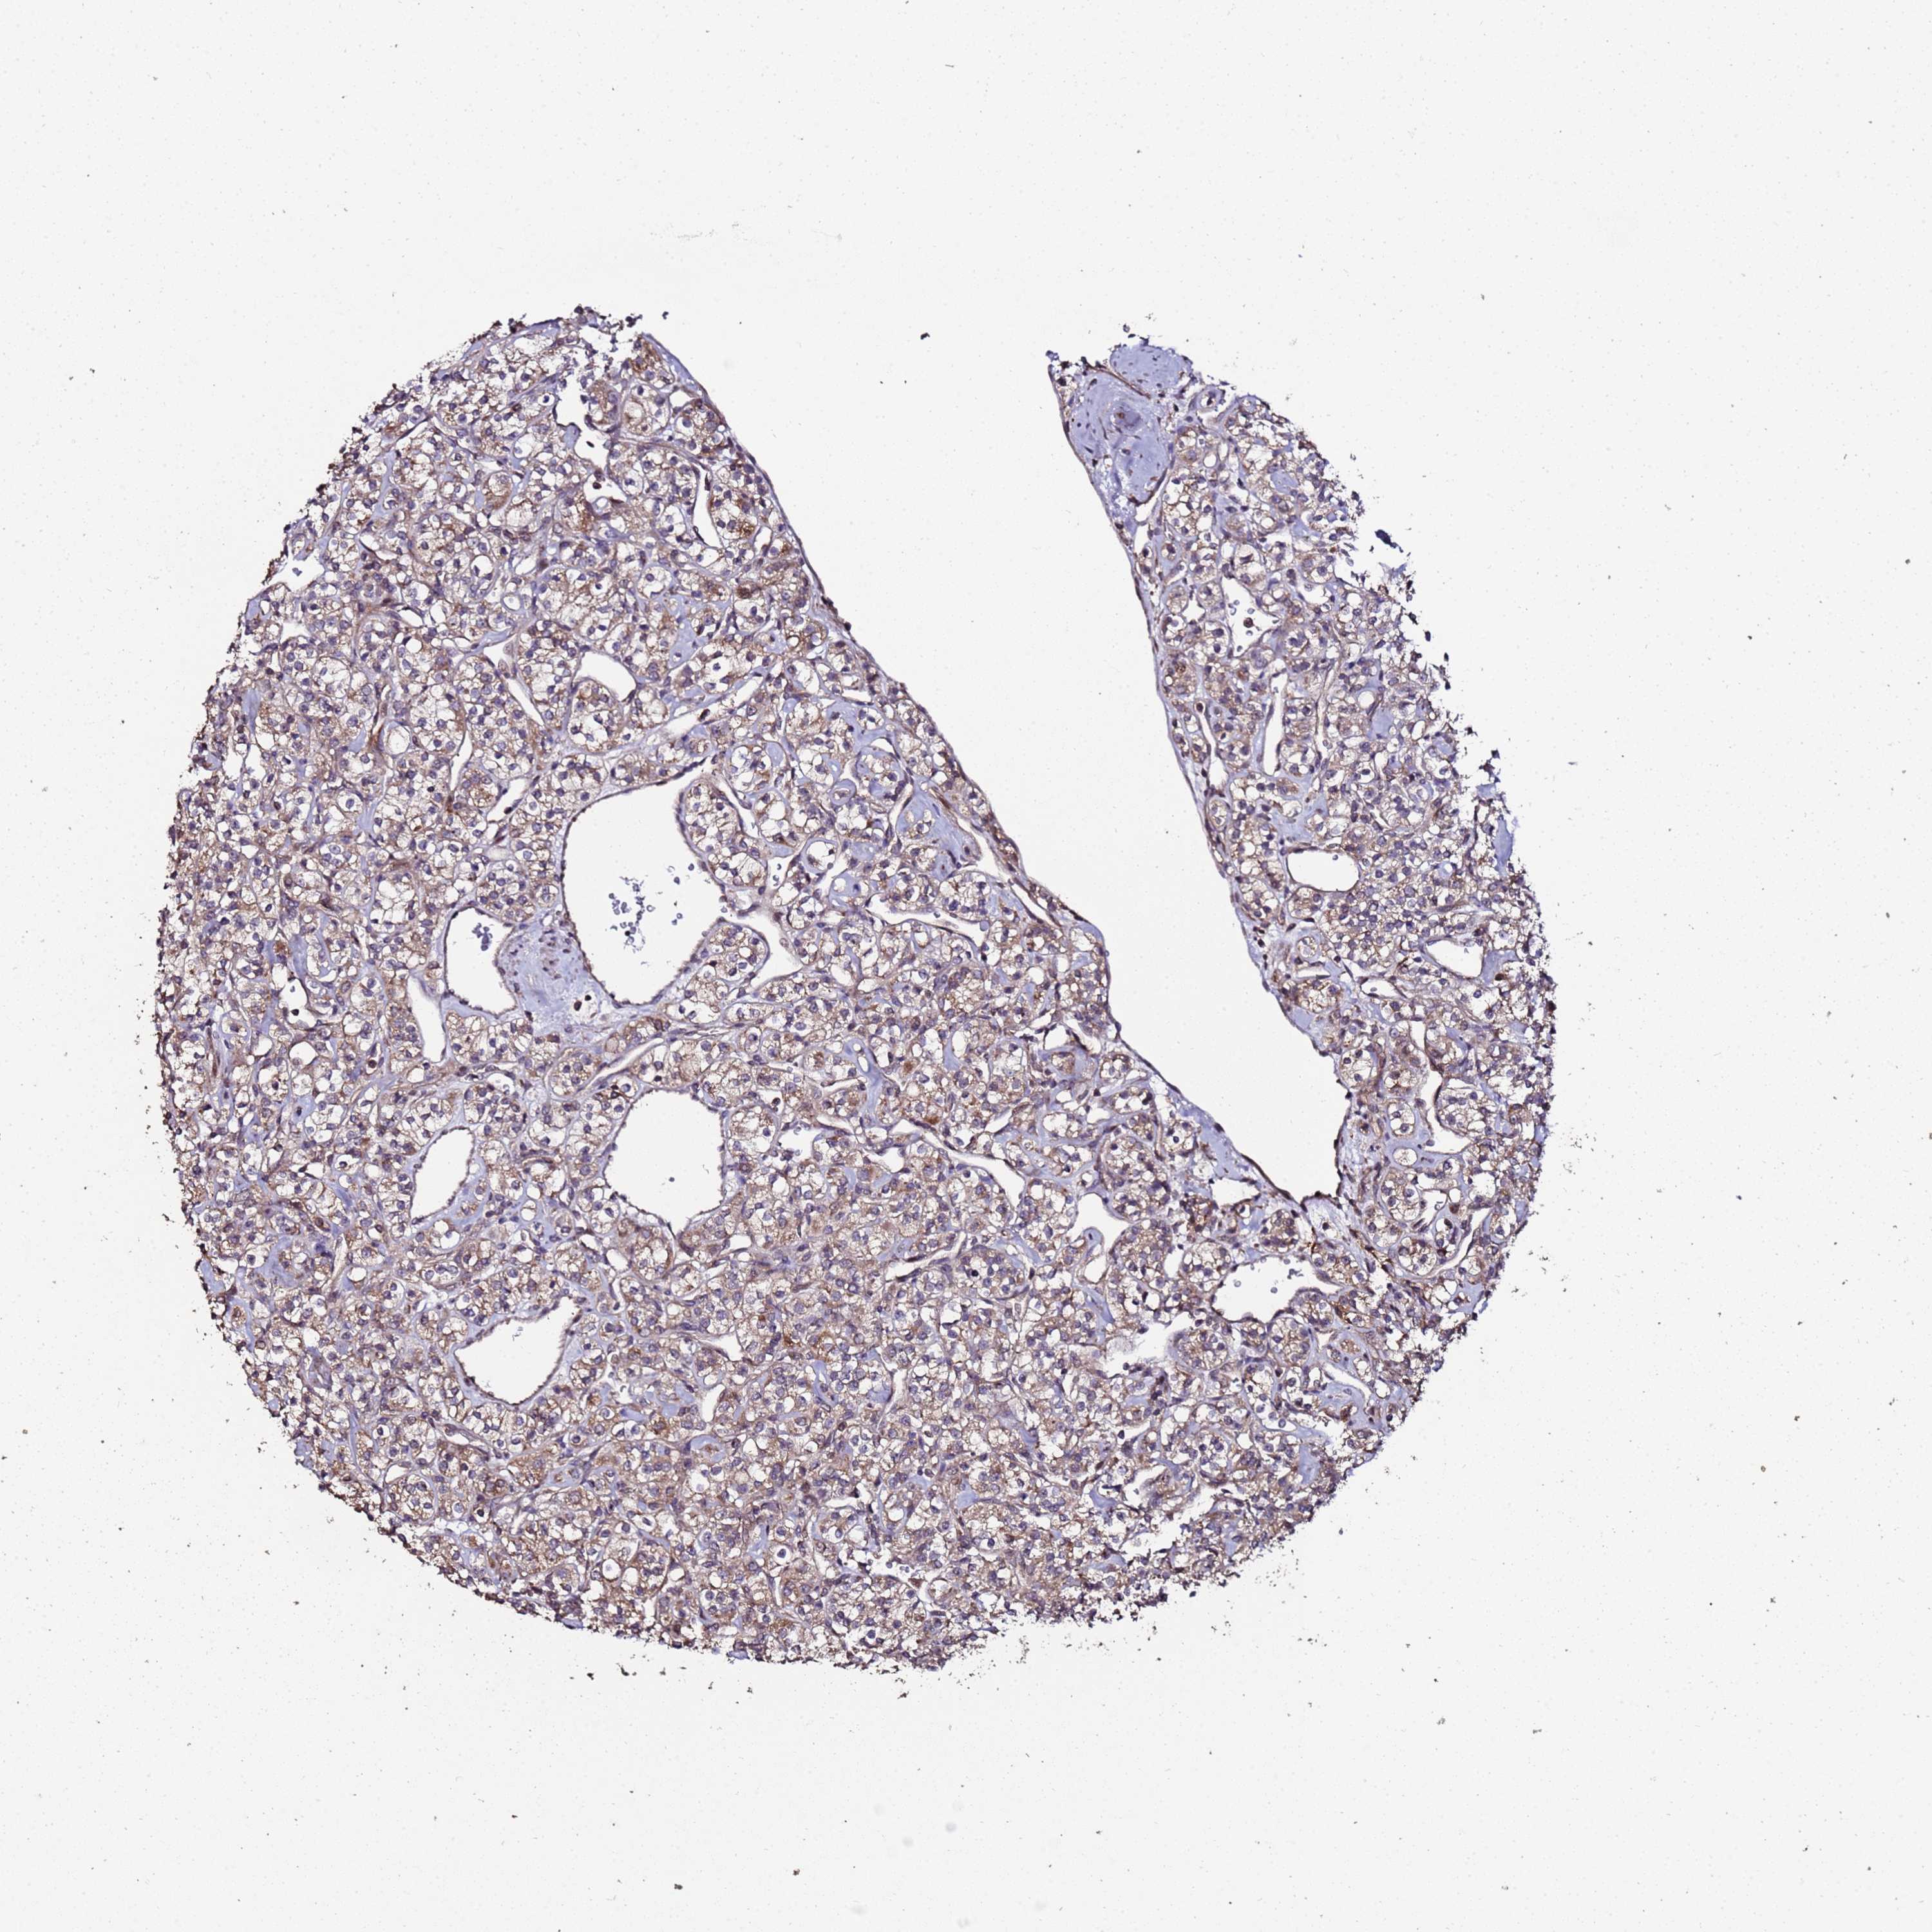

KIDNEY RENAL CLEAR CELL CARCINOMA (VALIDATION) - Interactive survival scatter ploti

The Survival Scatter plot shows the clinical status (i.e. dead or alive) for all individuals in the patient cohort, based on the same data that underlies the corresponding Kaplan-Meier plots. Patients that are alive at last time for follow-up are shown in blue and patients who have died during the study are shown in red.

The x-axis shows the expression levels (FPKM) of the investigated gene in the tumor tissue at the time of diagnosis. The y-axis shows the follow-up time after diagnosis (years). Both axes are complimented with kernel density curves demonstrating the data density over the axes. The top density plot shows the expression levels (FPKM) distribution among dead (red) and alive patients (blue). The right density plot shows the data density of the survived years of dead patients with high and low expression levels respectively, stratified using the cutoff indicated by the vertical dashed line through the Survival Scatter plot. This cutoff is automatically defined based on the FPKM cutoff that minimizes the p-score. The cutoff can be changed by dragging the vertical line or by entering a cutoff value in the square labeled "Current cut-off".

Under the Survival Scatter plot the p-score landscape (black curve; left axis) is shown together with dead median separation (red curve; right axis). Dead median separation is the difference in median mRNA expression between patients who have died with high and low expression, respectively. It is calculated as follows: median FPKM expression of dead patients with high expression - median FPKM expression of dead patients with low expression. This is intended to aid the user in visually exploring custom cutoffs and the associated p-scores and dead median separation.

Individual patient data is displayed and can be filtered by clicking on one or more of the category buttons on the top of the page. Categories describing expression level and patient information include: high, low, alive, dead, female, male and tumor stages. The scale of the x-axis can be toggled between linear and log-scale by clicking on the "x log" button. Mouse-over function shows TCGA ID, patient information and mRNA expression (FPKM) for each patient.

& Survival analysisi

Kaplan-Meier plots summarize results from analysis of correlation between mRNA expression level and patient survival. Patients were divided based on level of expression into one of the two groups "low" (under cut off) or "high" (over cut off). X-axis shows time for survival (years) and y-axis shows the probability of survival, where 1.0 corresponds to 100 percent.

PRODH is potential prognostic, high expression is favorable in Kidney Renal Clear Cell Carcinoma (validation)

Best expression cut offi

Based on the FPKM value of each gene, patients were classified into two groups and association between prognosis (survival) and gene expression (FPKM) was examined. The best expression cut-off refers the FPKM value that yields maximal difference with regard to survival between the two groups at the lowest log-rank P-value. Best expression cut-off was selected based on survival analysis .

When clicking on this number, the vertical dashed line indicating cut-off, the interactive survival plot, and the Kaplan-Meier curve will be adjusted to show results based on the best expression cut-off.

: 2.04

TCGA RNA samplesi

RNA-seq data is reported as average FPKM (number Fragments Per Kilobase of exon per Million reads), generated by the The Cancer Genome Atlas (TCGA) .

Normal distribution across the dataset is visualized with box plots, shown as median and 25th and 75th percentiles. Points are displayed as outliers if they are above or below 1.5 times the interquartile range. FPKM values of the individual samples are presented next to the box plot.

Average pTPM 8.0

Number of samples 100